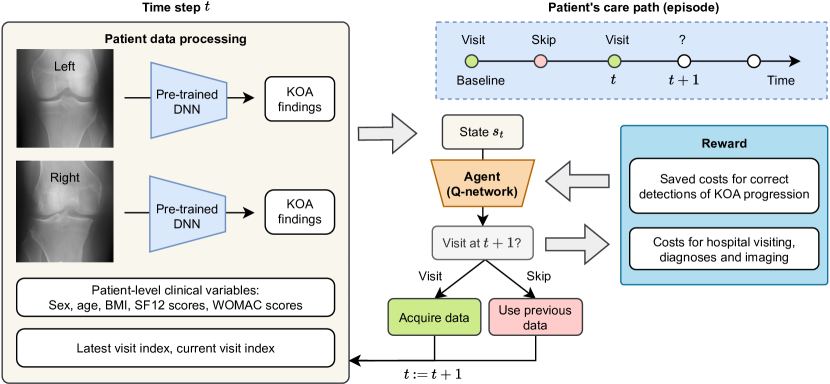

In this work, we develop an AS methodology for KOA using RL. We utilize RL to make sequential decisions based on the interactions between a decision-making agent and an environment simulating a clinical trial or another setting where patients need to be observed on an interval basis for a prolonged period of time. The overview of our method is depicted in Figure 1, and the specific contributions of our work are:

To elaborate on our implementation of AS via Q-learning-based RL, we first define the state space and describe the reward function design. Subsequently, we provide details on the dataset used to construct the RL environment, the architecture of the model, and the considered hyper-parameters.

State space

We define the state as a combination of patient-level clinical variables, radiographic findings, and time indices of data acquisition (0 – baseline examination, 1 – 1-year follow-up, and so forth). The included clinical variables describe common risk factors: age, sex, and Body Mass Index (BMI). Furthermore, we used the Western Ontario and McMaster Universities Arthritis Index (WOMAC) to quantify the patient’s symptoms, the physical score of the 12-Item Short Form Survey (SF12) to quantify the overall patient’s physical condition, binary code about the occurrences of past knee injury and surgery. Previous studies have demonstrated that these factors are significantly associated with KOA progression [21, 34, 55].

The radiographs were automatically evaluated by a pre-trained DL model that extracts the Kellgren and Lawrence grading (KLG) system to derive KOA severity level [36]. The KLG scale comprises 5 categories (from 0 to 4) that represent no OA, doubtful, mild, moderate, and severe OA, respectively. The graphical illustration of the KLG scale is provided in Figure 3. In our setup, we utilized the grades and their probabilities generated by a DL-based method developed for this task [50].

Finally, beyond the clinical variables and image-related information (i.e. KLG), we included the time information as a part of the state, specifically, the current time index and the time index of the latest data acquisition. The clinical variables and the radiographic findings are updated in the state once the agent chooses a follow-up action.

4.3 Agent

We designed our Q-Network to process the state revealed by the environment (i.e. multi-modal input data) and predict the Q-value for each action. The input data, excluding the KOA status, were normalized across the dataset by subtracting the mean and dividing by the standard deviation. The KOA status, as presented in Section 2.3, is a vector of probabilities extracted from a pre-trained deep neural network (DNN), where each probability corresponds to a particular severity grade. We employed the Semixup model [50] to extract image features and KLG probabilities. Whereas the imaging feature dimension of each radiograph was , the vector of KLG probabilities had a size of .

We first combined the KLG probability vectors from both knees and the vector of clinical variables, resulting in an input vector of size . The Q-Network was a simple neural network a simple neural network (batch norm of the inputs followed by a single hidden layer with dropout probability of and sigmoid activation function, followed by a linear output layer with 2 heads). The network’s output was a -element vector representing Q-values of actions for each time step.